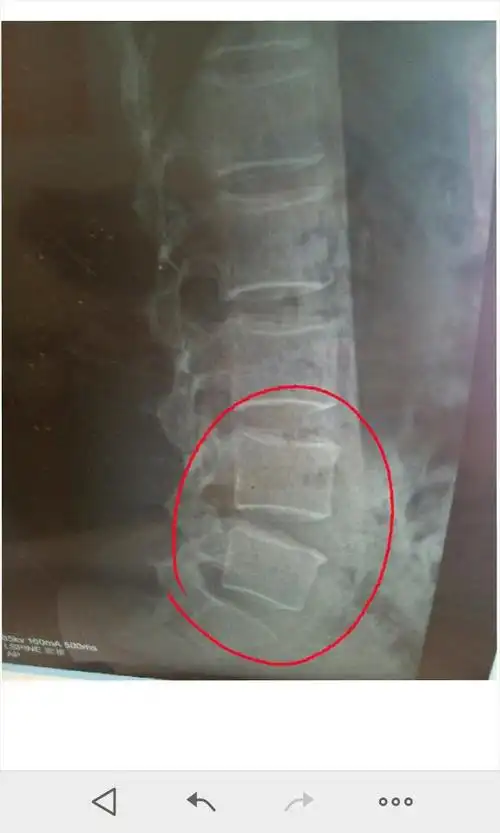

术前检查:x线 腰椎侧弯 骨质增生

腰椎骨质增生

这是我爸在医院拍的片子,骨质增生,腰椎盘突出,有医生说做手术有一定